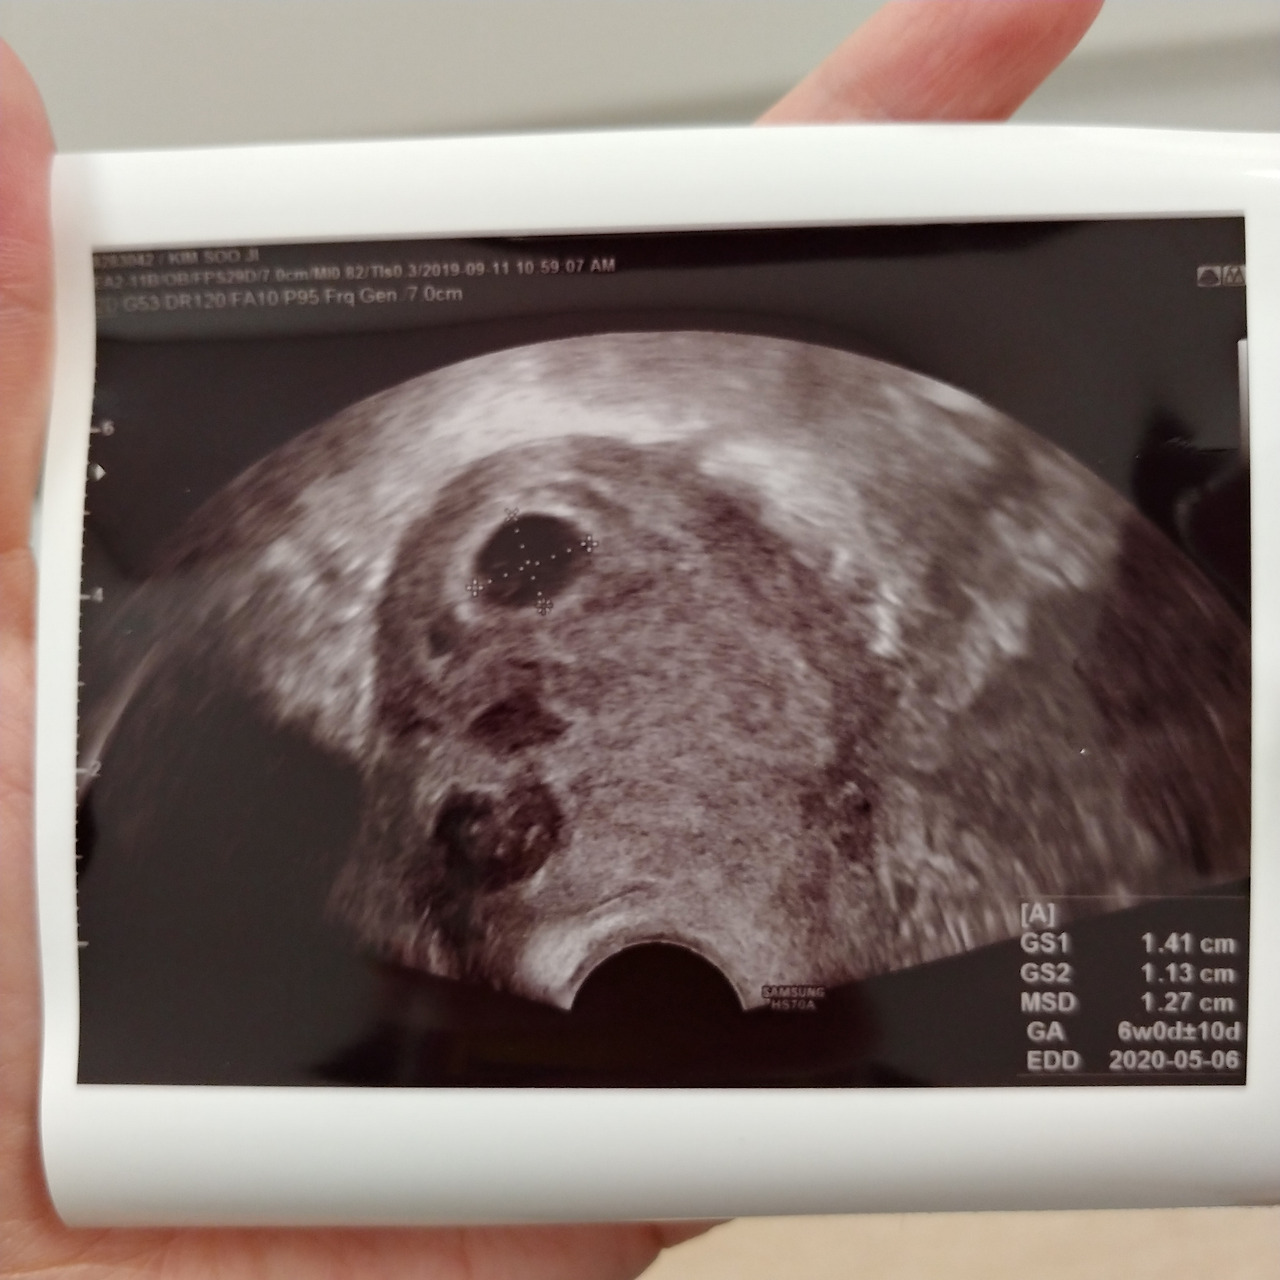

2019년 9월 11일 수요일, 우리 '하나뿐인' 복이는 이랬다. 눈을 가늘게 뜨고 봐야 보일 듯 말 듯한 작은 크기. 저렇게 작고 희미한 검은 점 속에서 한 생명이 숨 쉬려는 참이다. 저런 ''이 점점 자라나서 결국 한 명의 '사람'이 된다고 하니 참으로 믿기 어려운 일이다.